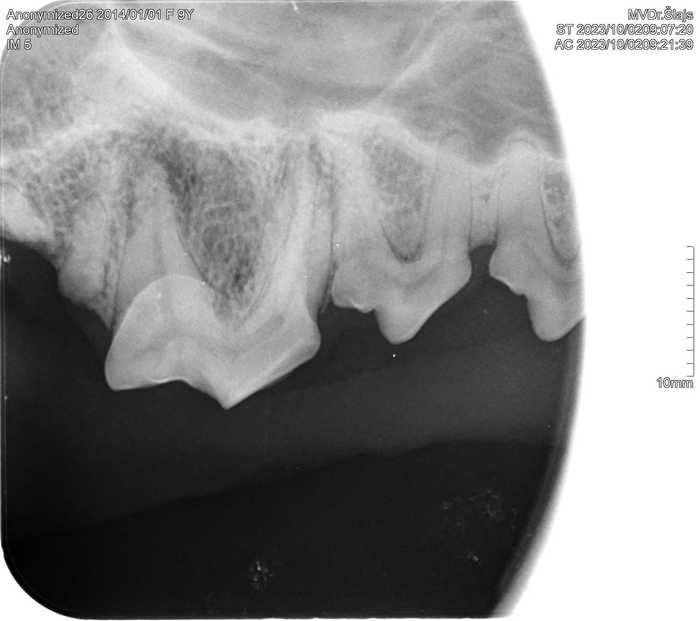

Již nyní má na našem pracovišti RTG vyšetření nezastupitelné místo během vyšetření zubů a dutiny ústní u králíků, morčat, psů i koček.

Zubní intraorální RTG nám umožňuje přesnější diagnostiku onemocnění zubů, díky čemuž je úspěšnější i léčba.

S pomocí intraorálního RTG s vysokým rozlišením jsme schopni ještě před vlastním zubařským zákrokem přesně stanovit diagnózu a rozhodnout, zda a kde přesně provést chirurgický zákrok.

Díky posouzení zubních kořenů a stavu kostního podkladu zubů můžeme provést zákrok přesně v místě, kde je potřeba a stanovit následnou léčbu tak, aby hojení probíhalo co nejrychleji a pacient nemusel zbytečně podstupovat opakované ošetření.